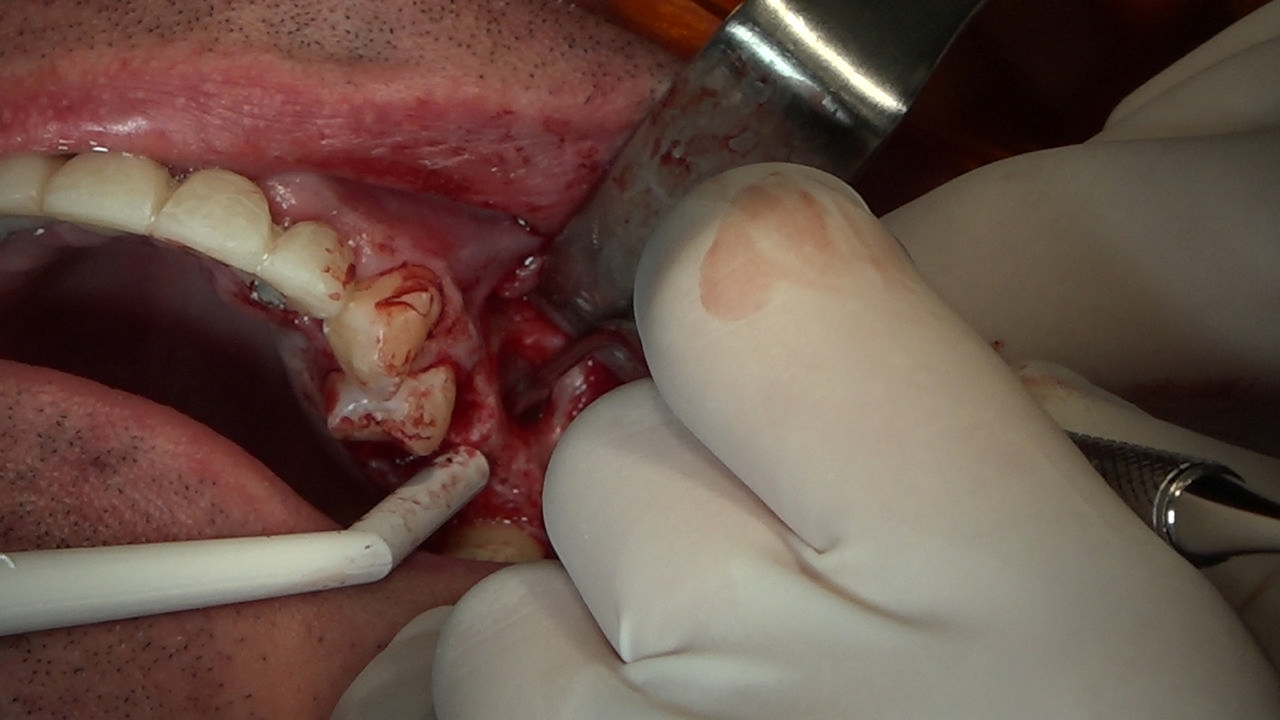

PRACTICULUM IMPLANTOLOGII - SEZON X - SESJA 7

7 Sesja X Sezonu Practiculum Implantologii, w której brali udział kursanci z Grupy A i B, obejmowała implantacje wykonane systemem Axiom, procedury regeneracyjne tkanki kostnej i zabieg sinus lift oraz procedury implantoptotetyczne. Ten zakres szkolenia poprowadziła dr Małgorzata Piotrowska. Protetyka na implantach, to finalny etap leczenia implantologicznego decydujący o uzyskaniu harmonijnego łuku zębowego, okluzji oraz szczelności połączeń, a więc zadowoleniu Pacjenta i powodzeniu całego procesu leczenia.

Jego sednem jest wybór optymalnego rozwiązania rekonstrukcji protetycznej uwzględniający bardzo wiele czynników o charakterze mechanicznym, funkcjonalnym i estetycznym, związanych ze stanem tkanki kostnej, jamy ustnej i uzębienia. Odbywa się już na etapie tomografii komputerowej i jest ściśle powiązany z częścią chirurgiczną, ponieważ prawidłowe zaplanowanie pracy i usytuowania implantów wspomagane plastyką tkanek miękkich, to dla procedur protetycznych baza wyjściowa. Zasady te są jak najbardziej oczywiste, zarówno przy samodzielnym wykonywaniu leczenia implantologicznego, jak i przy podziale zadań dla chirurga i protetyka, czyli pracy w duecie.